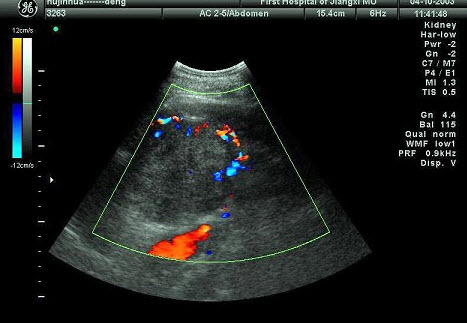

某患者肝脏发现肿块回声,根据CDFI声像图表现,最可能的诊断是()

A.肝血管瘤

B.肝脓肿

C.肝炎性假瘤

D.肝囊肿

E.肝癌